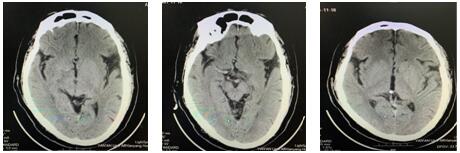

16:26急查頭顱CT示:右側額葉皮質區(qū)急性期腦梗死,結合患者癥狀體征考慮腦梗死急性期。請示NICU王偉偉主任,立即啟動綠色通道。

17:21 DSA示:右側大腦中動脈、前動脈閉塞。與患者家屬談話,簽字后立即行中動脈、前動脈取栓術。